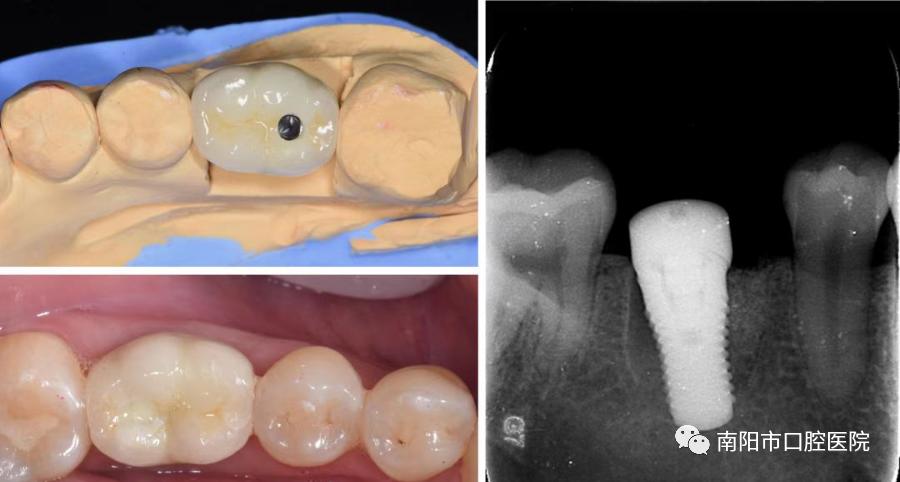

根管治疗后全瓷冠修复

拔除后种植牙修复